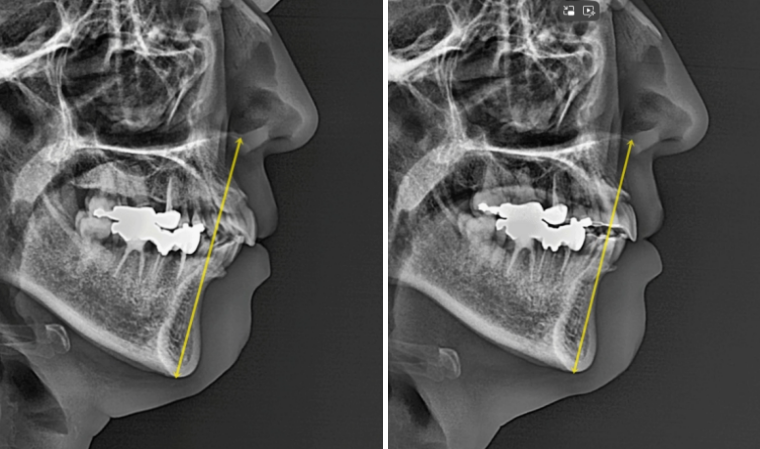

치료 전 후 엑스레이 중첩을 보면 재교정 효과가 잘 보입니다.

전체치열 함입과 후방이동으로 아래턱뼈의 자가회전이 꽤 많은 양 일어났습니다.

일반적으로는 2mm 정도를 목표로 치료하지만 3mm가량 일어났습니다.

무턱처럼 보이던 부분이 개선이 되고 호두턱이 풀려 아랫입술에 턱으로 이어지는 라인이 자연스럽니다.

자가회전이 되면 턱끝이 올라가고 정면에서 봤을 때 하관의 세로 길이가 짧아져서 작아보입니다.

또 자가회전으로 인하여 턱끝이 소량 앞으로 나오게 됩니다.

그래서 아래턱이 작은 무턱에서는 무턱까지 해소가 되니 함입교정을 적극 추천드립니다.